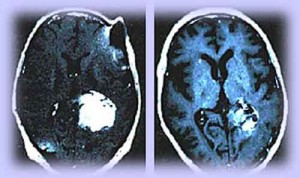

GlioblastomaMultiforme

Il glioblastoma multiforme, il piu’ comune e aggressivo tipo di tumore cerebrale, potrebbe nascere da cellule mature del cervello che sono ritornate al loro stato embrionale, indifferenziato.La ricerca del Salk Institute for Biological Studies di La Jolla e’ stata pubblicata sulla rivista ‘Science’. La sorprendente scoperta potrebbe avere implicazioni per il trattamento di questi tumori, dato che prevede che qualunque tessuto tumorale cellulare rimosso dalla chirurgia e dalla chemioterapia potrebbe potenzialmente rigenerare il tumore.

Precedenti modelli avevano suggerito che i tumori si generassero principalmente da cellule staminali neurali indifferenziate. Dinorah Friedmann-Morvinski e colleghi hanno mostrato ora che, nei topi, cellule neurali pienamente mature e differenziate possono trasformarsi in indifferenziate da geni oncogeni. Questi geni innescano cambiamenti genetici che rimandano la cellula matura indietro nel tempo, facendola tornare al stato indifferenziato, simile a quello di una cellula staminale. Questa condizione puo’ poi far partire e sostenere la crescita di un tumore.